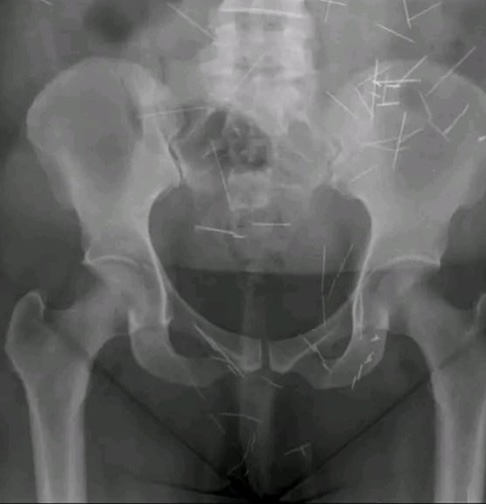

De início, a mulher foi encaminhada para o Hospital Estadual da Mulher (Hemu), mas pela a idade declarada, foi reencaminhada para o Hospital da Criança e do Adolescente (Hecad). Após uma avaliação, foi constatado que ela estava bem e sem dor, mas que possuía várias agulhas dentro do corpo, que poderiam ter sido engolidas ou introduzidas.

Imagem: PM